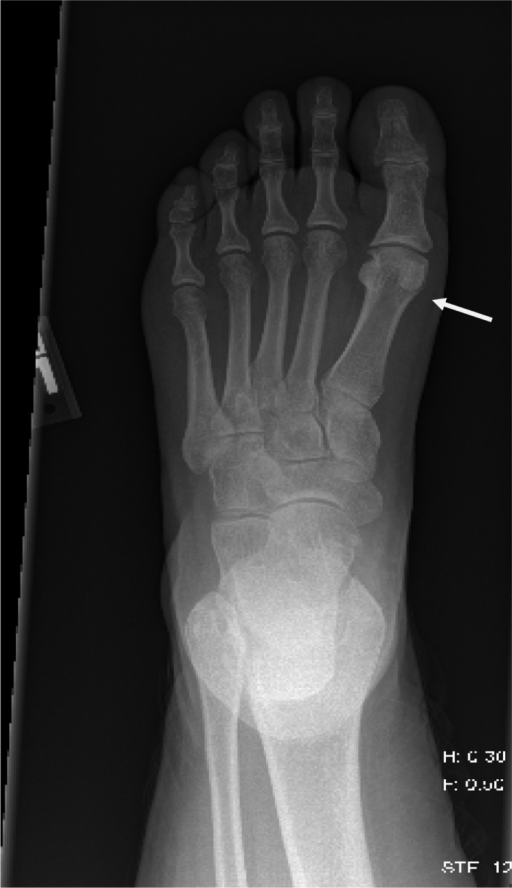

Role of teriparatide in accelerating metatarsal stress fracture healing: a case series and review of literature. Raghavan P, Christofides E - Clinical medicine insights. Endocrinology and diabetes (2012)